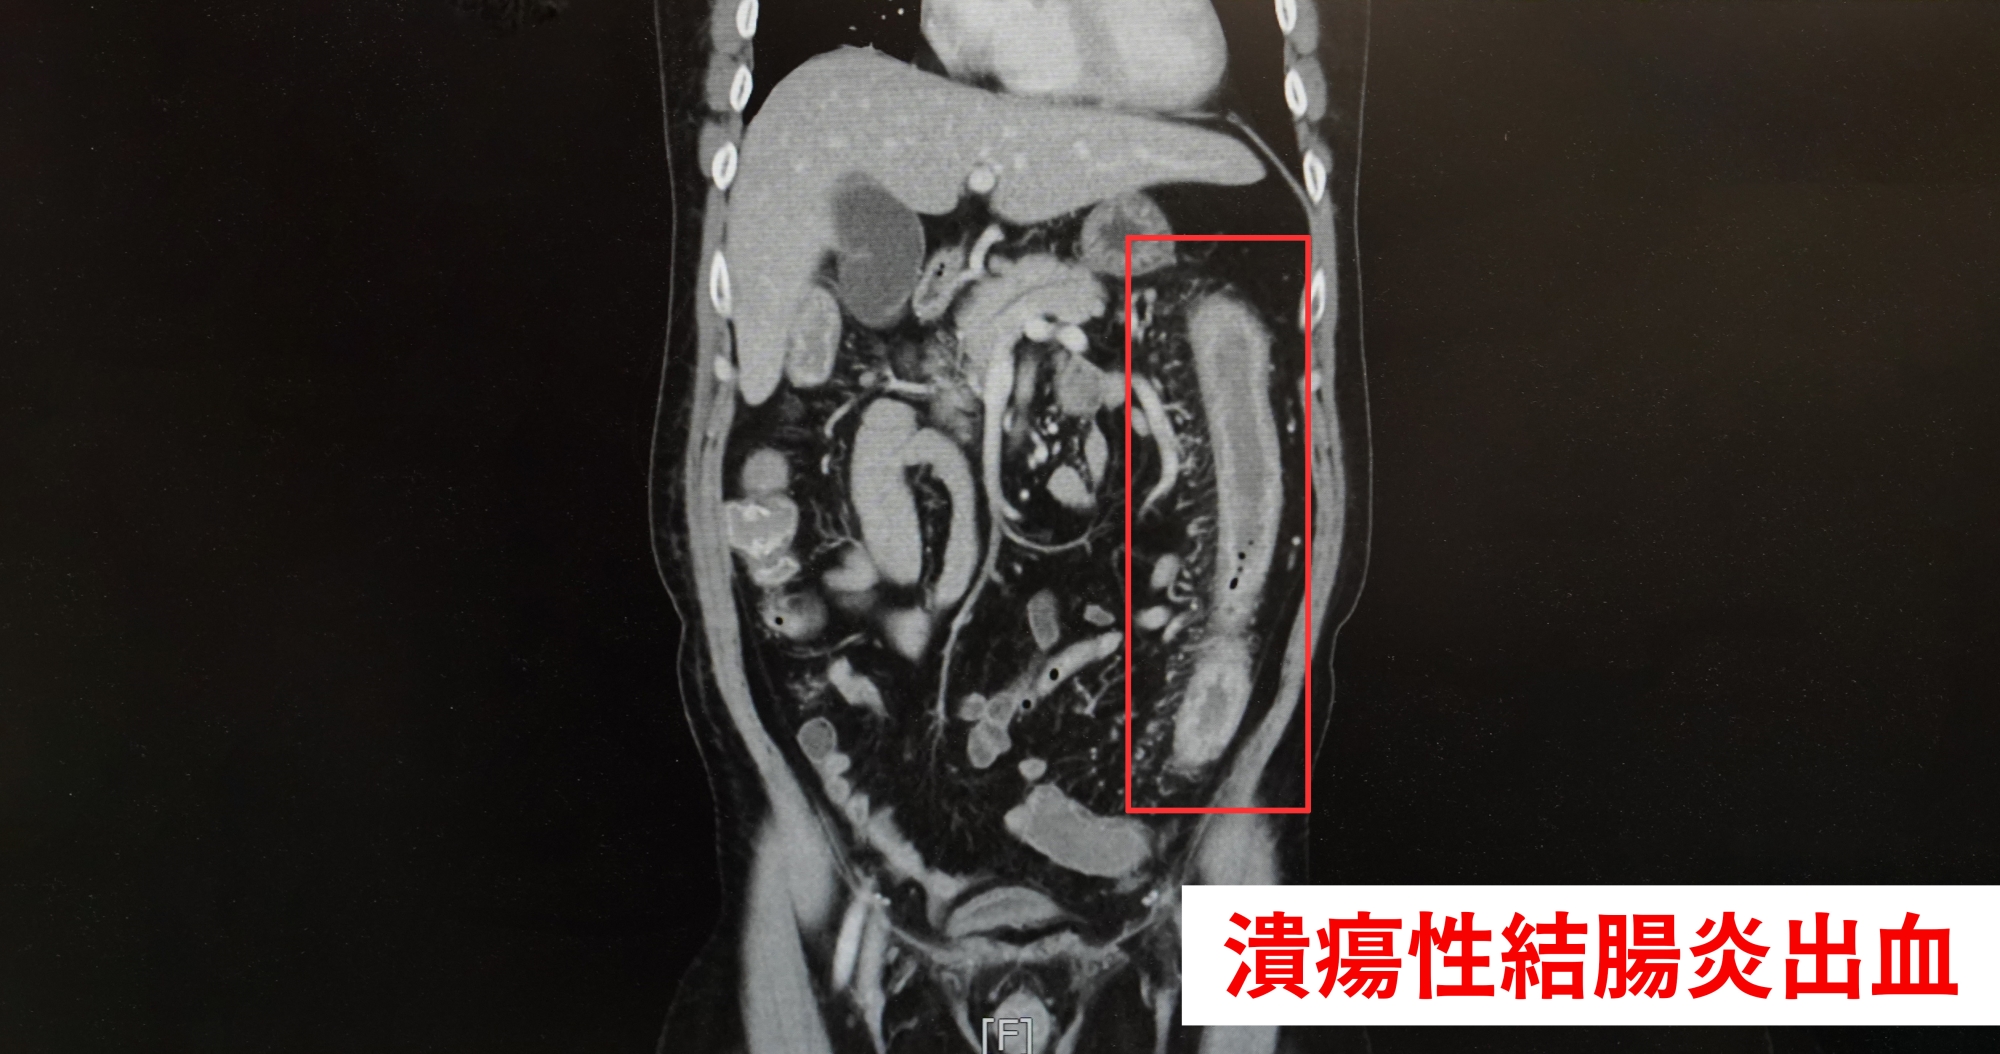

潰瘍性結腸炎出血影像 圖∕中醫大新竹醫院

潰瘍性結腸炎是一種慢性發炎性腸道疾病,主要影響結腸和直腸黏膜,常伴隨腹瀉、腹痛、血便等症狀。出血是此病常見的併發症,主要是因黏膜潰瘍破裂,如果是急性發作期病情會惡化,引起其他併發症,如中毒性巨結腸、腸穿孔、或結腸癌等,引起出血,長期使用類固醇或抗凝劑,可能增加出血風險。

蘇俞豪表示,潰瘍性結腸炎是一種慢性發炎性腸道疾病,主要影響結腸和直腸黏膜,常伴隨腹瀉、腹痛、血便等症狀。出血是此病常見的併發症,主要是因黏膜潰瘍破裂,如果是急性發作期病情會惡化,引起其他併發症,如中毒性巨結腸、腸穿孔、或結腸癌等,引起出血,長期使用類固醇或抗凝劑也可能增加出血風險。